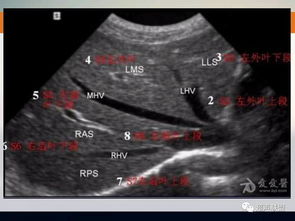

- I段:尾状叶,位于肝脏的后方,形状像一条尾巴。

- II段:左外叶上段,位于肝脏的左侧,形状像一把伞。

- III段:左外叶下段,位于肝脏的左侧,形状像一把勺子。

- IV段:左内叶,位于肝脏的左侧,形状像一颗心。

- V段:右前叶下段,位于肝脏的右侧,形状像一把剑。

- VI段:右后叶下段,位于肝脏的右侧,形状像一把锤子。

- VII段:右后叶上段,位于肝脏的右侧,形状像一把弓。

- VIII段:右前叶上段,位于肝脏的右侧,形状像一把扇子。

- CT检查:首先找出肝脏的三大静脉:肝中静脉、肝左静脉、肝右静脉;找出门静脉及其分叉部位。门静脉分叉可以区分上段和下段,即肝S5/S8、S6/S7,门静脉分叉以上为S8、S7;肝右静脉和肝中静脉之间是右前叶,肝右静脉以后是右后叶;一般规律,从CT上看,最先看到的是S8,然后是S2、3,肝左外叶以肝裂为界,比较容易辨认,左内叶为肝裂和肝中静脉之间区域,胆囊往下的层次是S5,最后的层面一般是肝S6,下腔静脉和门静脉夹着的是尾状叶,即S1。